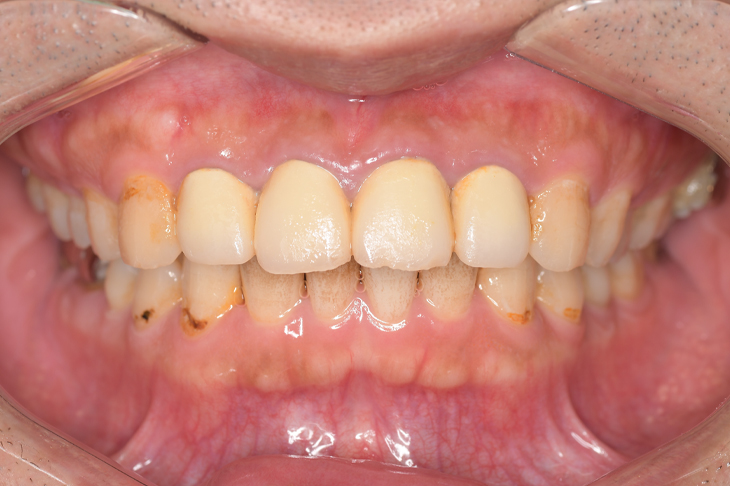

Before

After

基本情報

| 年齢・性別 | 30代・男性 |

| 主訴 | 歯石を取りたい |

| 治療内容 | 超音波スケーラーでの歯石除去 |

| 治療期間 | 60分 |

| 治療費 | 初診料を含め約4,500円 |

| リスク・副作用 | 歯ぐきに違和感や痛みを覚える場合がある。 1週間程度、歯を磨くといつもより出血することがある。 腫れていた歯ぐきが引き締まることで歯ぐきが下がった様に見える。 歯ぐきが下がることで歯がみしやすくなることがある。 一時的に歯の動揺(ゆれ)が増す場合がある。 |